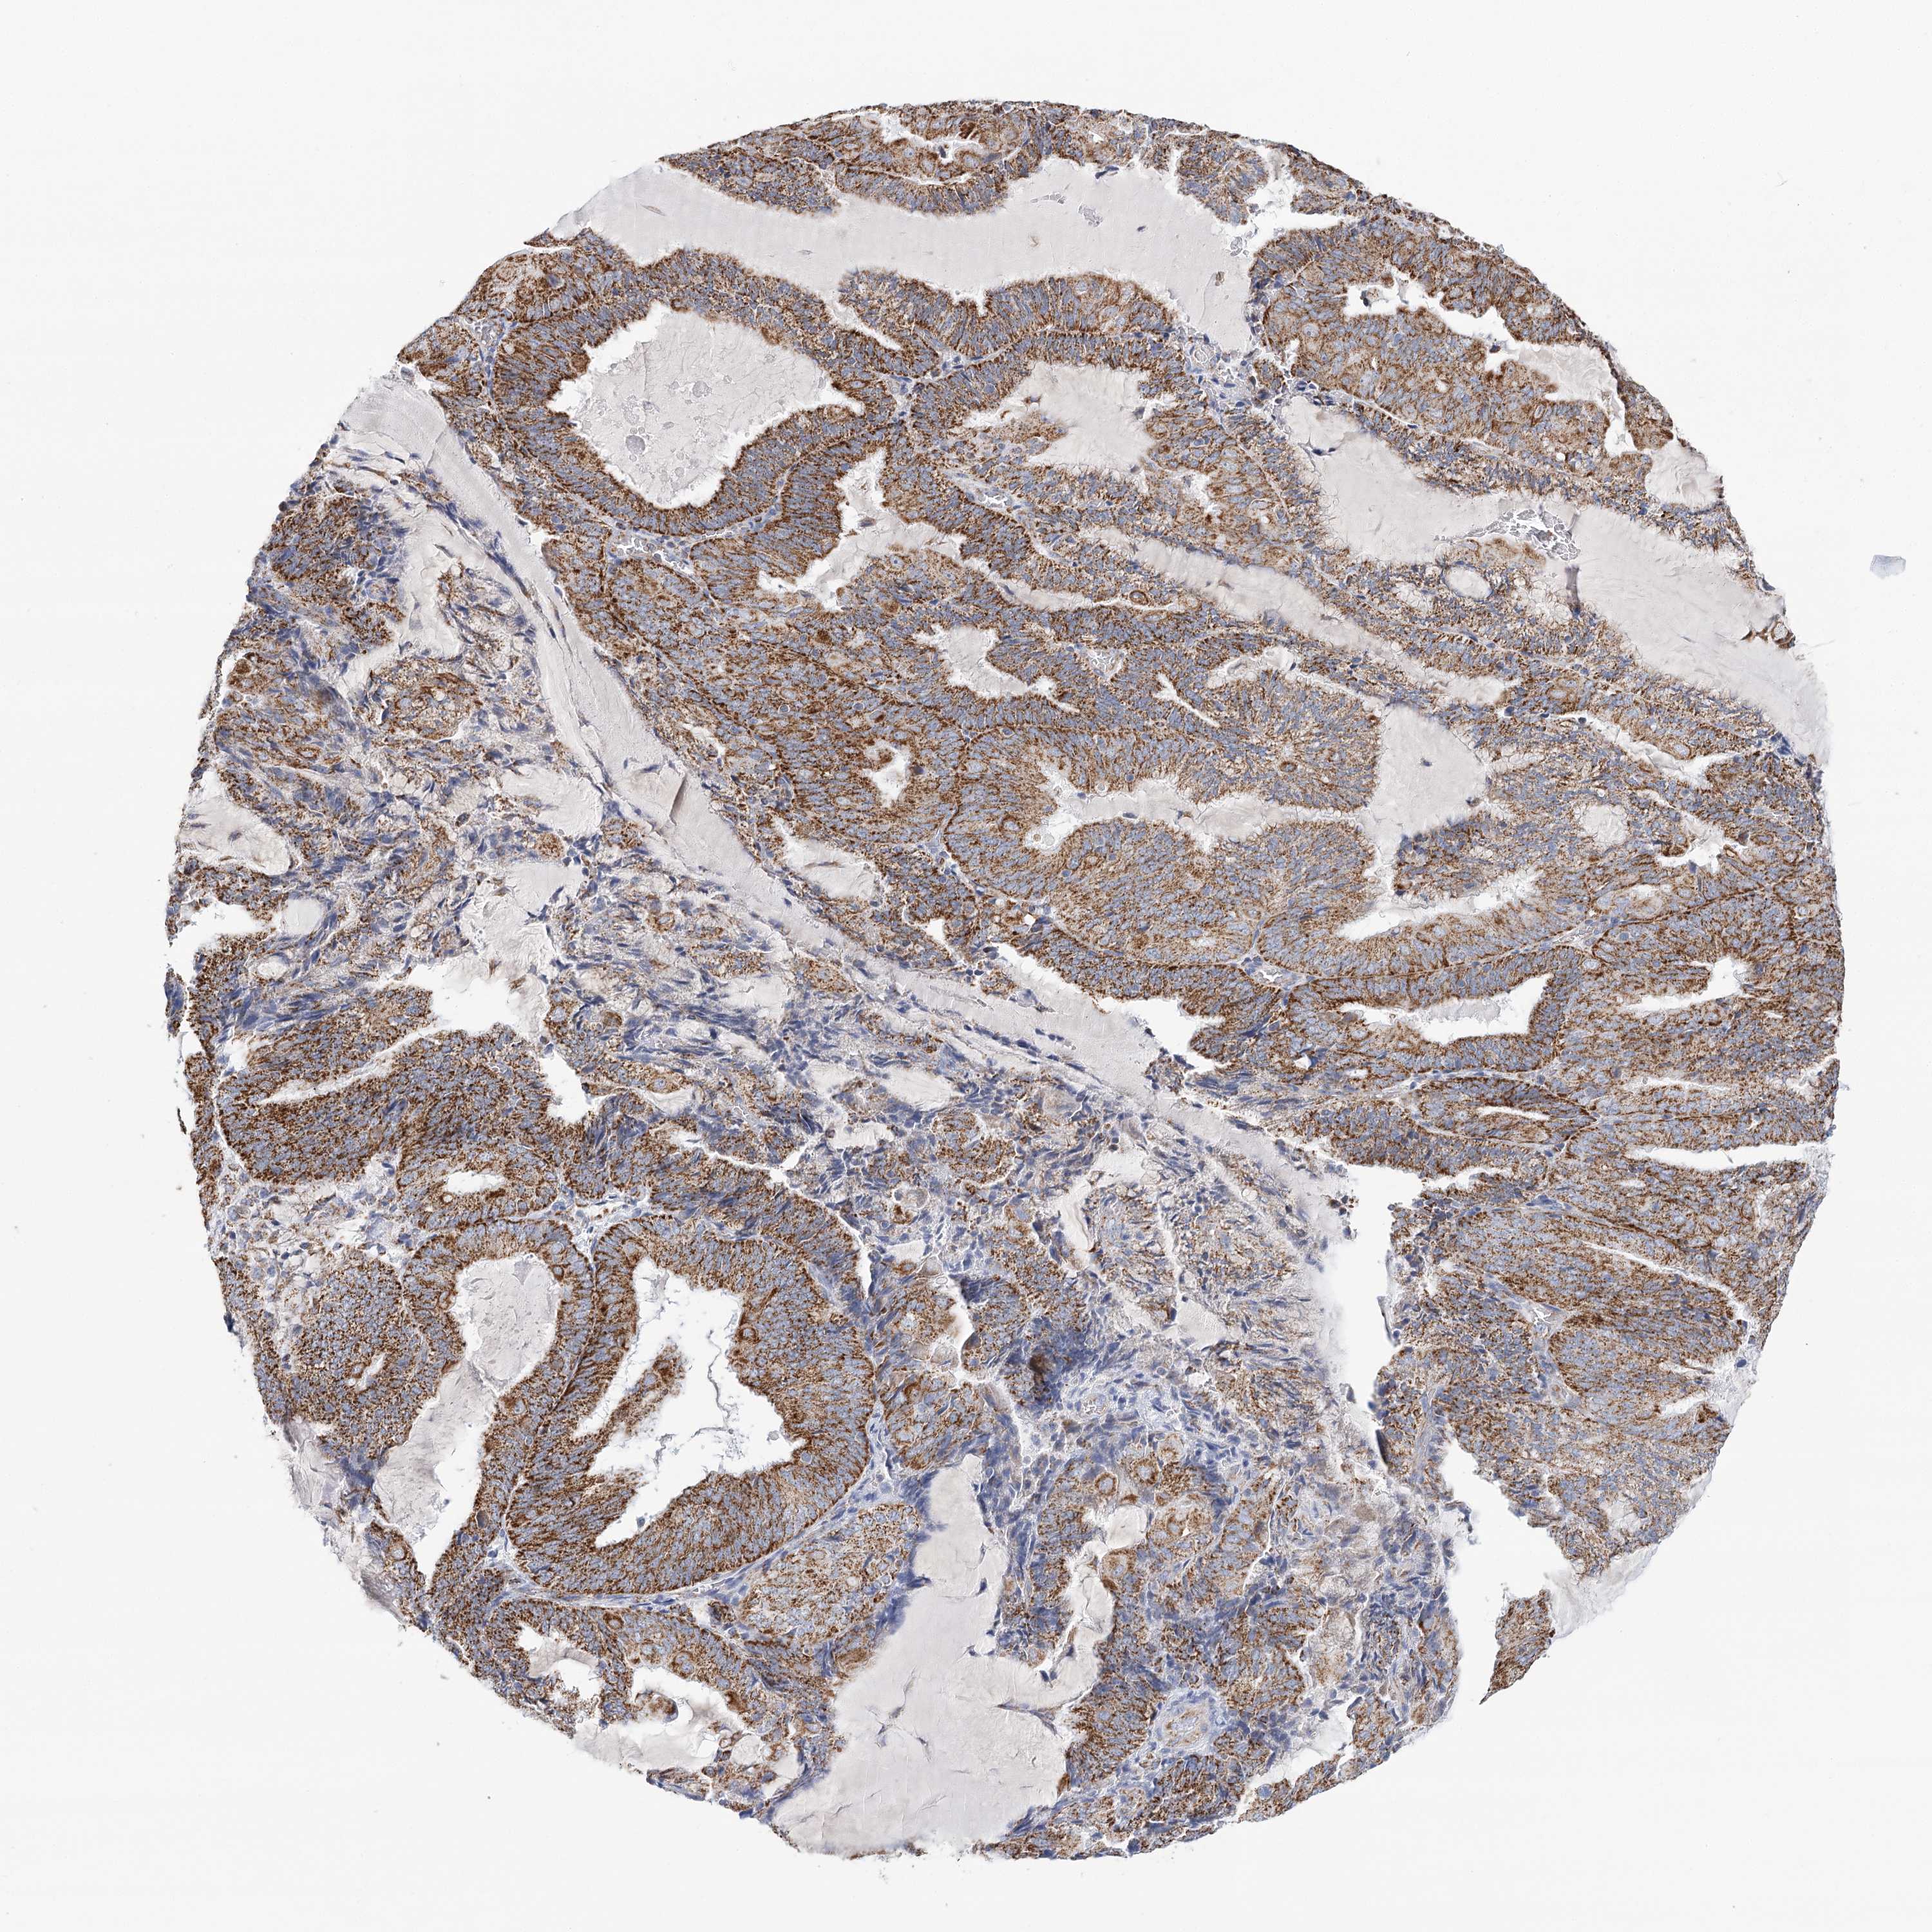

ENDOMETRIAL CANCER - Protein expressioni

A mouse-over function shows sample information and annotation data. Click on an image to view it in a full screen mode. Samples can be filtered based on level of antibody staining by selecting one or several of the following categories: high, medium, low and not detected. The assay and annotation is described here.

Note that samples used for immunohistochemistry by the Human Protein Atlas do not correspond to samples in the TCGA dataset.

Antibody stainingi

Antibody staining in the annotated cell types in the current human tissue is reported as not detected, low, medium, or high, based on conventional immunohistochemistry profiling in selected tissues. This score is based on the combination of the staining intensity and fraction of stained cells.

Each image is clickable and will lead to virtual microscopy that enables deeper exploration of all samples and also displays staining intensity scores, fraction scores and subcellular localization as well as patient and tissue information for each sample.

Antibody HPA032060

Antibody HPA032062

Antibody CAB034116

Staining

High

Medium

Low

Not detected

Intensity

Strong

Moderate

Weak

Negative

Quantity

>75%

75%-25%

<25%

None

Location

Nuclear

Cytoplasmic/membranous

Cytoplasmic/membranous,nuclear

Adenocarcinoma, NOS

Adenocarcinoma, metastatic, NOS